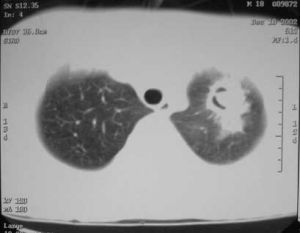

一位52歲的病患,已有十幾年的糖尿病史,三個月前發現有陸陸續續的咳血現象,曾經到居家附近的醫院就醫,經肺部X光檢查發現她的兩側上肺葉有空洞、浸潤現象,被高度懷疑是罹患肺結核,經兩周的藥物治療仍未見改善。這是罕見的侵犯性肺曲病,罹患此病的患者會有咳血、體重劇降的明顯症狀,症狀與肺結核極為相似。

以患者的肺部X光片上肺葉有大片浸潤及空洞情形判斷,雖然首先要懷疑是肺結核,但經痰液抹片檢查卻是陰性,表示患者可能並非肺結核引起的咳血等症狀,再以支氣管鏡檢查,赫然發現患者兩側上肺葉長滿一簇簇的黃色狀腫瘤般病灶,塞滿兩側上肺葉的氣管,經病理切片檢查,證實是罹患了罕見的侵犯性肺曲菌病。

這位罹患肺曲菌病的女性患者,經七十天的服藥,再經肺部X光追蹤檢查,其原先肺部空洞、浸潤的現象以消失,以支氣管鏡檢查,原先一簇簇黃色腫瘤狀的病灶已不存在,病情完全康愈。